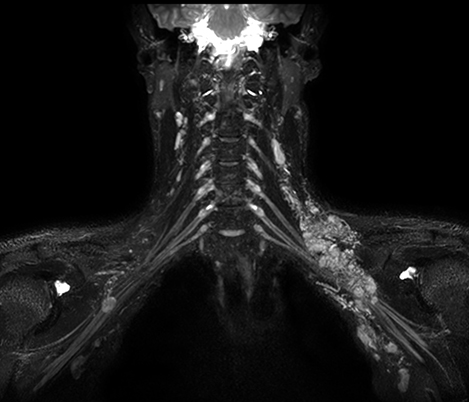

At the Rothschild Foundation Hospital in Paris we run most of our post contrast T1 TSE sequences with MSDE black blood suppression because it is easier to interpret the data with the high signal from small vessels removed to optimize conspicuity of contrast enhancing lesions.

Dr. Savatovsky, Fondation Rothschild, Paris, France